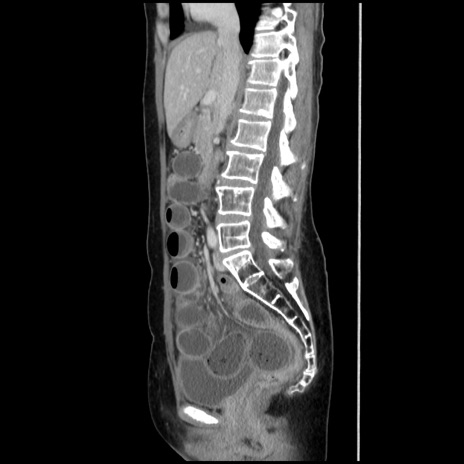

症例32(矢状断像)

【症例】40歳代 女性

【主訴】上腹部痛、嘔気・嘔吐

【現病歴】約9時間前頃から急に上腹部痛、嘔気、嘔吐が出現。改善しないため救急要請。

【既往歴】子宮頚癌(広汎子宮全摘術、放射線療法)、腸閉塞

【身体所見】腹部:平坦、軟、腸雑音亢進、上腹部を中心に腹部全体に圧痛あり。

【データ】WBC 8400、CRP 0.03